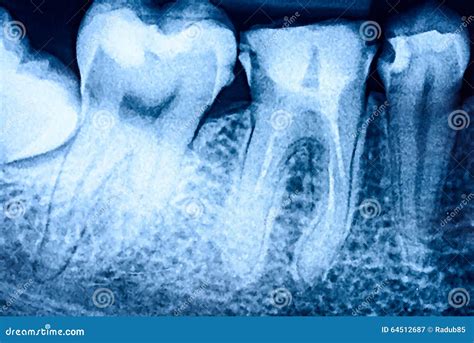

Periapical Viewing the entire tooth from crown to root to check for abscesses.

When looking at your own X-rays on a monitor, you might find them confusing. Dentists are trained to identify specific visual cues. In a tooth decay X-ray, enamel—the hardest substance in your body—appears as a bright white or light gray area. Healthy bone also shows up in varying shades of white. When tooth decay is present, it appears as a darker, shadowy spot on the image.

This happens because the demineralization caused by bacteria makes the tooth structure less dense, allowing more X-ray radiation to pass through the area. The less dense the tissue, the darker it appears on the radiograph. If your dentist points out a dark spot on your X-ray, they are identifying an area where the mineral content of your tooth has been compromised by acid-producing bacteria.